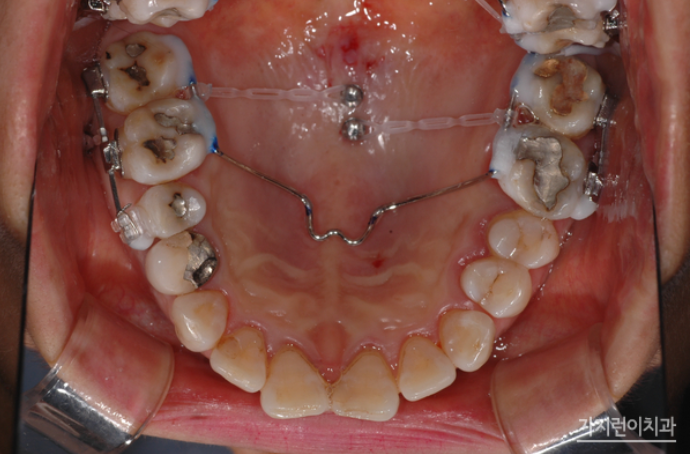

치아 상실 시 치료를 미루다가 방치하는 경우가 생각보다 많은데요. 치아 상실을 방치하면 빈 공간으로 치아가 이동하면서 치열이 무너질 수 있고, 또 잇몸 퇴축 현상이 일어나면서 추후 임플란트 시 문제가 될 수 있습니다. 그래서 환자분의 경우 치료를 통해 하악 구치부에 임플란트를 식립할 수 있었는데요. 상악 구치부의 함입을 위해 미니스크류를 식립했고 충분한 힘이 전해질 수 있도록 설계했습니다. 원래대로라면 하악 좌우 대구치 2개 및 제2소구치까지 모두 여섯 개의 임플란트가 필요했지만 이렇게 설계하면 임플란트를 4개만 심을 수 있었는데요.

이후 치료가 시작된 지 1년이 지났고 상악 작은 어금니를 발치해 안정적인 교정을 진행하셨는데요. 안정적인 교정을 위해 상악 설측교정 장치는 두개의 와이어를 사용하는 탄댐설측교정 장치로 진행했습니다.